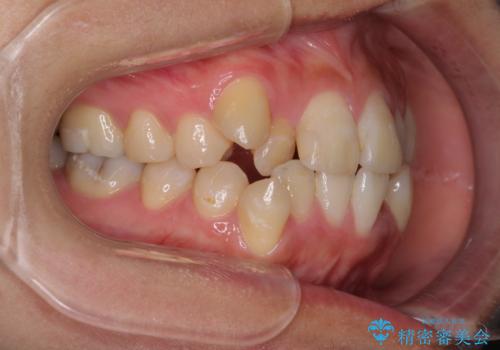

- 上下の八重歯を気にして来院された患者様です。

八重歯の後ろの歯を1歯抜歯し、補助装置(リンガルアーチ)を用いて八重歯の位置を改善し、その後インビザラインにより矯正治療を行うこととしました。

右側のみ上下小臼歯を抜歯したため、上下の正中が右にずれてしまう可能性があります。

また、元々右側は上下が咬み合っていないため、矯正をしても咬み合わないことも考えられました。